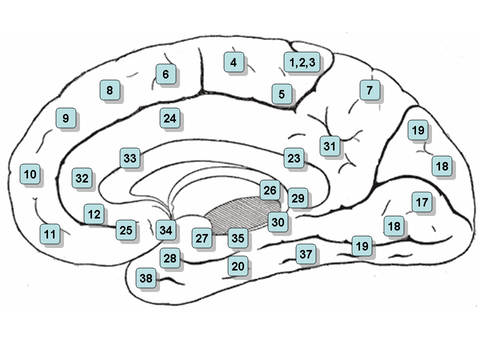

Medial surface, person facing to the left. Nucleus accumbens is very roughly in Brodmann area 34 | |

The nucleus accumbens (NAc or NAcc), also known as the accumbens nucleus or as the nucleus accumbens septi (Latin for nucleus adjacent to the septum) is a region in the basal forebrain rostral to the preoptic area of the hypothalamus.[1] The nucleus accumbens and the olfactory tubercle collectively form the ventral striatum, which is part of the basal ganglia.[2] Each cerebral hemisphere has its own nucleus accumbens, which can be divided into two structures: the nucleus accumbens core and the nucleus accumbens shell. These substructures have different morphology and functions.

The nucleus accumbens is an aggregate of neurons which is described as having an outer shell and an inner core.[6]

Core

The nucleus accumbens core is the inner substructure of the nucleus accumbens.

Location: The nucleus accumbens core is part of the ventral striatum, located within the basal ganglia.